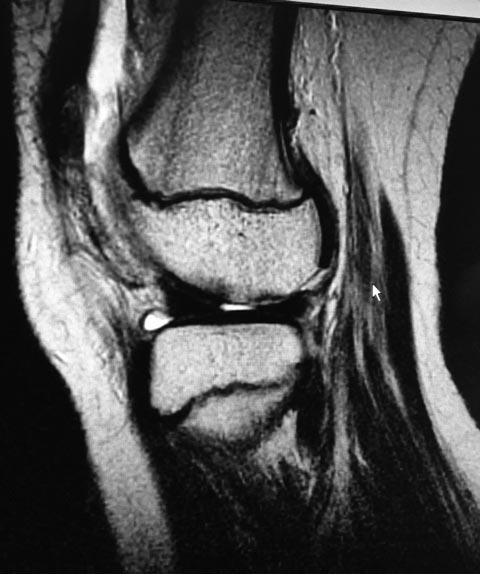

Девочка 10 лет. Травма 1 месяц назад упала на горке. Лечилась

консервативно. По данным МРТ имеется остеохондральный дефект наружного

мыщелка бедренной кости и свободный костно-хрящевой фрагмент размером 3

см. в диаметре. План лечения: артротомия, рефиксация по возможности. На